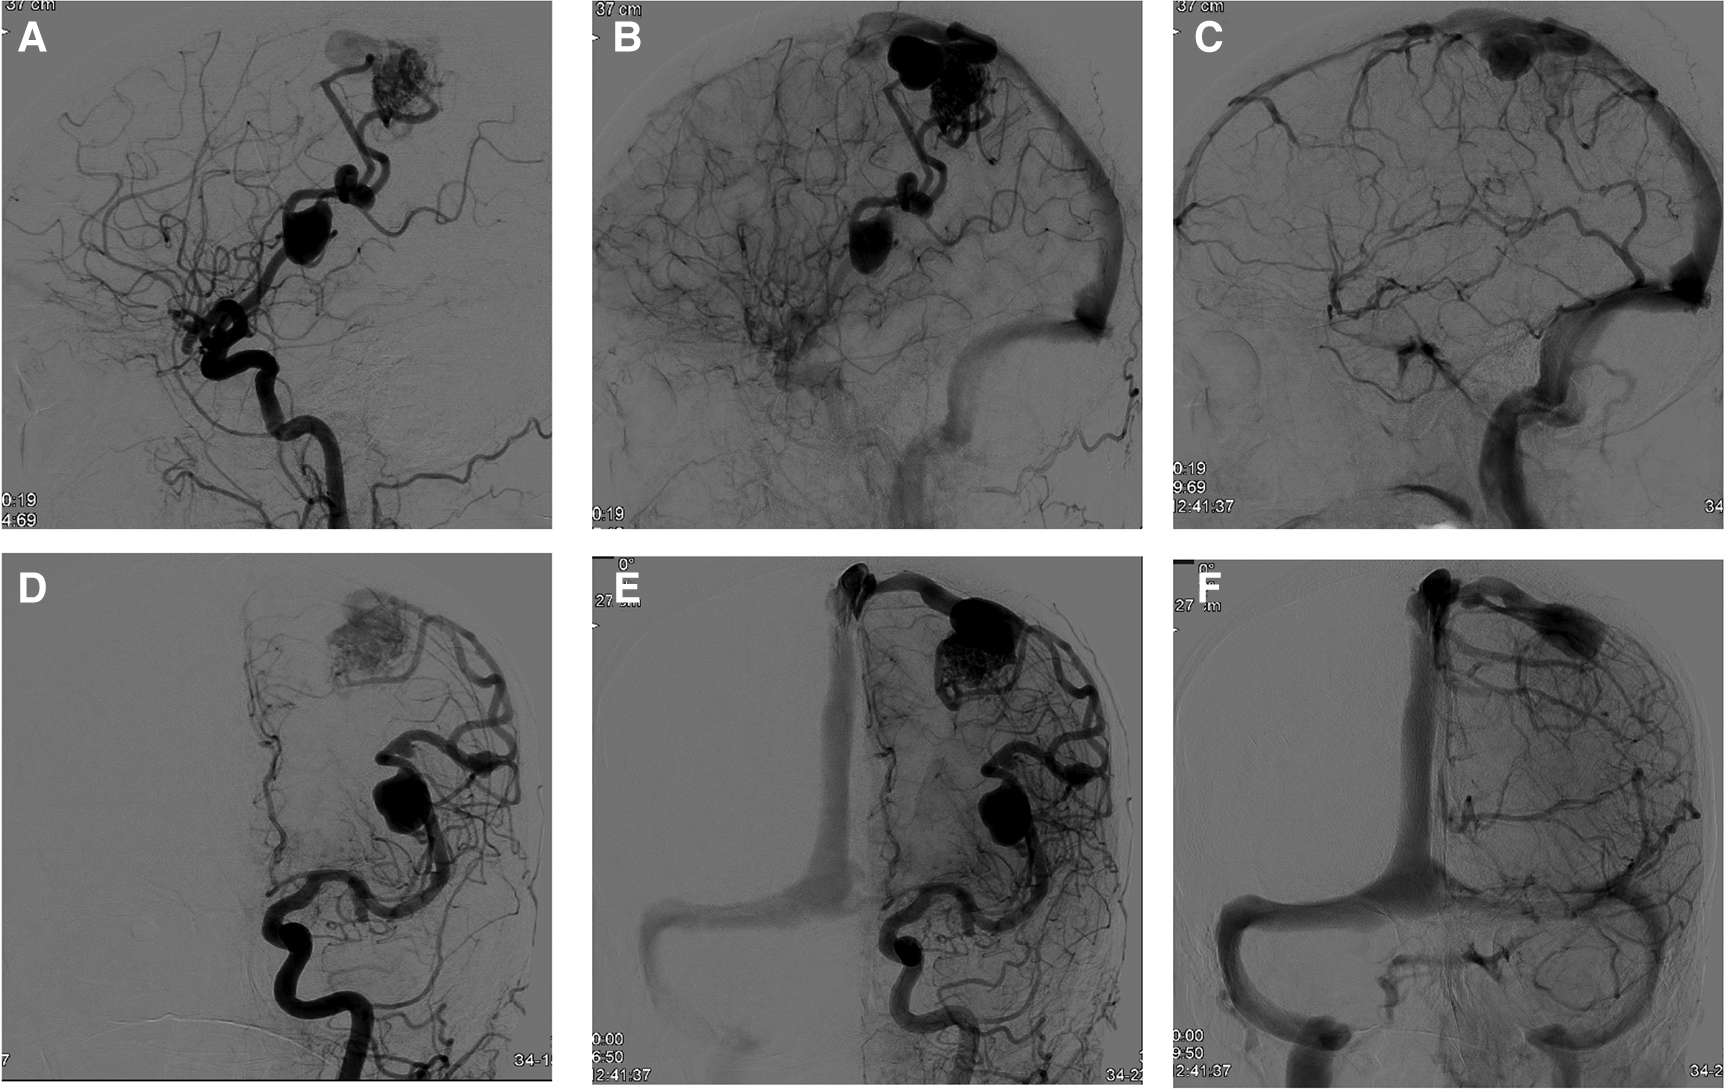

Figure 1

DSA at baseline and at 6 months’ follow-up. (A,B) Sagittal angiogram showing coil embolization of a ruptured PComA on the right side. (C) Coil embolization of the unruptured AComA aneurysm at 6 months’ follow-up without missing sings of PComA reperfusion (both MRRC, class II).